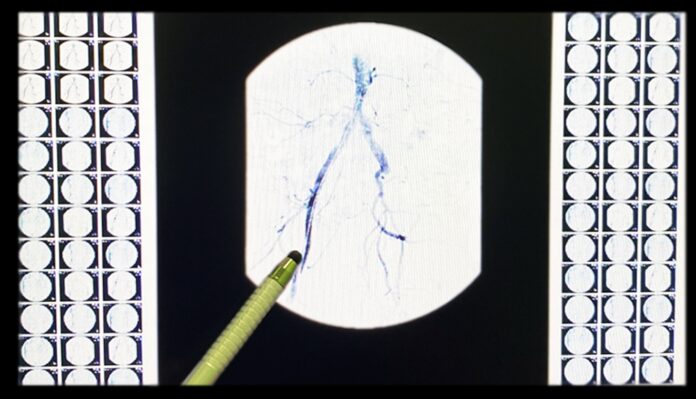

Для оценки состояния сосудов была проведена коронарная ангиография. Усложнял ситуацию необычно большой диаметр артерии.

Бригада врачей успешно провела операцию, и сейчас пациент здоров. Коронарную ангиографию объясняет врач-кардиолог отделения неотложной кардиологии с блоком реанимации и интенсивной терапии Ирина Цыганкова: «Коронарная ангиография – малоинвазивное исследование сосудов сердца, в ходе которого врач получает изображение сосудов с помощью введения в артерии рентгеноконтрастного вещества. Сегодня данная процедура считается одной из самых информативных в кардиологии для диагностики патологии сосудов. С её помощью можно обнаружить серьезные проблемы в работе сердечно-сосудистой системы».